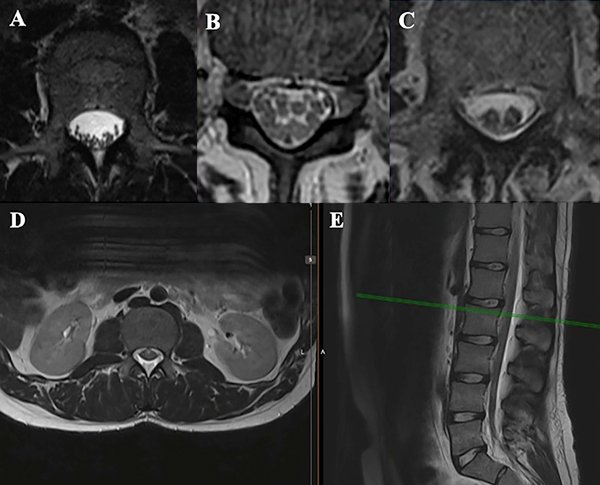

Se presenta el caso de una paciente de 21 años de edad, con antecedentes de infección por VIH, sífilis, consumo de drogas ilícitas y alcohol, que consulta por parestesias en ambos miembros inferiores de 6 meses de evolución, a lo que agrega paraparesia y dificultad en la marcha en los últimos 3 meses, con empeoramiento progresivo. Al examen físico presentaba una paraparesia moderada, hipertonía, hiperreflexia e hipoestesia en todas las modalidades sensitivas en miembros inferiores con nivel sensitivo T4 y signo de Babinski bilateral, así como también dolor dorsal con irradiación a ambos miembros inferiores. En la resonancia magnética (RMN) de columna completa se observaba una imagen a nivel T1 a T3, hipointensa en T1, hiperintensa en T2 y STIR, sin captación de contraste endovenoso, con desplazamiento posterior de la médula espinal y adelgazamiento de la misma (Figura 1 y 2). Se interpretó el cuadro como un quiste aracnoidal asociado a una aracnoiditis adhesiva. En este contexto, debido a la progresión y severidad de los síntomas, se realizó laminotomía T1-T2-T3 y evacuación de la lesión quística en el mismo nivel (Figura 3). Se enviaron muestras de aracnoides a anatomía patológica, la cual demostró “fragmento de tejido dural con fibroesclerosis y vasocongestión”; a su vez se realizaron cultivos de gérmenes comunes, hongos, parásitos, tuberculosis y PCRs virales, los cuales resultaron negativos.

Figura 1: Resonancia magnética de la paciente, se observa lesión quística a nivel T1-T2-T3, con desplazamiento posterior de la médula espinal y adelgazamiento de la misma. A- En secuencia T1 se visualiza la lesión quística hipointensa; B- En secuencia T2, la lesión quística es hiperintensa; C- En STIR la lesión quística también es hiperintensa, correlacionándose con la señal del LCR.

Figura 2: RMN con corte sagital (A) y axiales a distintos niveles (B). Se observa el desplazamiento posterior de la médula espinal y el quiste anterior a la misma.